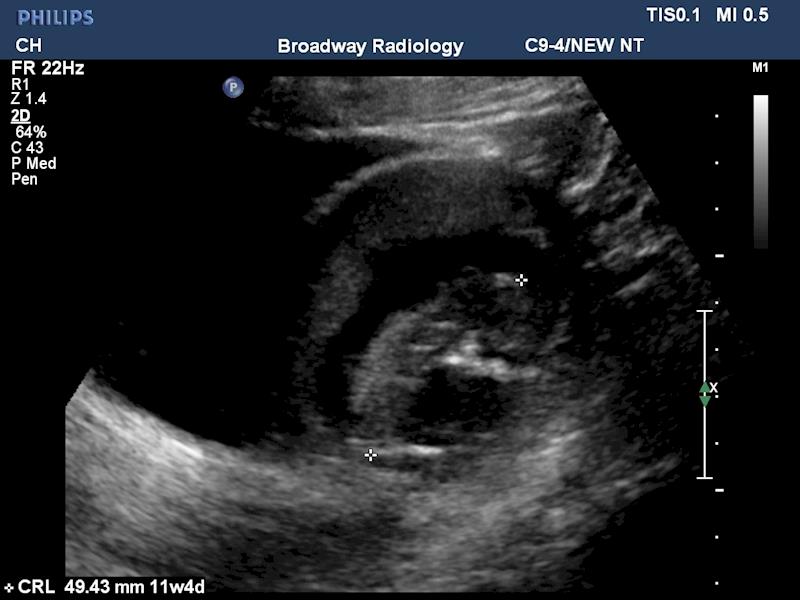

Potters Syndrome Ultrasound . A doctor can diagnose oligohydramnios sequence with an ultrasound. Potter syndrome refers to the typical physical appearance and associated pulmonary hypoplasia of a neonate as a direct result of. A routine specialized imaging technique called a fetal ultrasound may detect potter syndrome before birth. Using sound waves, an ultrasound will produce an image of the developing fetus and allow the clinician to visualize certain structures, such as the fetal kidneys, as well as the. An ultrasound can detect low levels of amniotic fluid and abnormal kidney development in the fetus. Potter syndrome is a fatal congenital disorder characterized by the changes in physical appearances of neonate due to oligohydramnios caused. The condition is the result of abnormal kidney growth and. Potter syndrome, also known as potter sequence, is a rare condition that affects how a fetus develops in the uterus. Serial ultrasounds should be used to monitor fetuses with suspected potter's syndrome.

An ultrasound can detect low levels of amniotic fluid and abnormal kidney development in the fetus. Potter syndrome, also known as potter sequence, is a rare condition that affects how a fetus develops in the uterus. Potter syndrome is a fatal congenital disorder characterized by the changes in physical appearances of neonate due to oligohydramnios caused. The condition is the result of abnormal kidney growth and. A routine specialized imaging technique called a fetal ultrasound may detect potter syndrome before birth. A doctor can diagnose oligohydramnios sequence with an ultrasound. Potter syndrome refers to the typical physical appearance and associated pulmonary hypoplasia of a neonate as a direct result of. Using sound waves, an ultrasound will produce an image of the developing fetus and allow the clinician to visualize certain structures, such as the fetal kidneys, as well as the. Serial ultrasounds should be used to monitor fetuses with suspected potter's syndrome.

Potters Syndrome Ultrasound Potter syndrome, also known as potter sequence, is a rare condition that affects how a fetus develops in the uterus. The condition is the result of abnormal kidney growth and. A routine specialized imaging technique called a fetal ultrasound may detect potter syndrome before birth. Potter syndrome is a fatal congenital disorder characterized by the changes in physical appearances of neonate due to oligohydramnios caused. A doctor can diagnose oligohydramnios sequence with an ultrasound. Serial ultrasounds should be used to monitor fetuses with suspected potter's syndrome. An ultrasound can detect low levels of amniotic fluid and abnormal kidney development in the fetus. Using sound waves, an ultrasound will produce an image of the developing fetus and allow the clinician to visualize certain structures, such as the fetal kidneys, as well as the. Potter syndrome refers to the typical physical appearance and associated pulmonary hypoplasia of a neonate as a direct result of. Potter syndrome, also known as potter sequence, is a rare condition that affects how a fetus develops in the uterus.